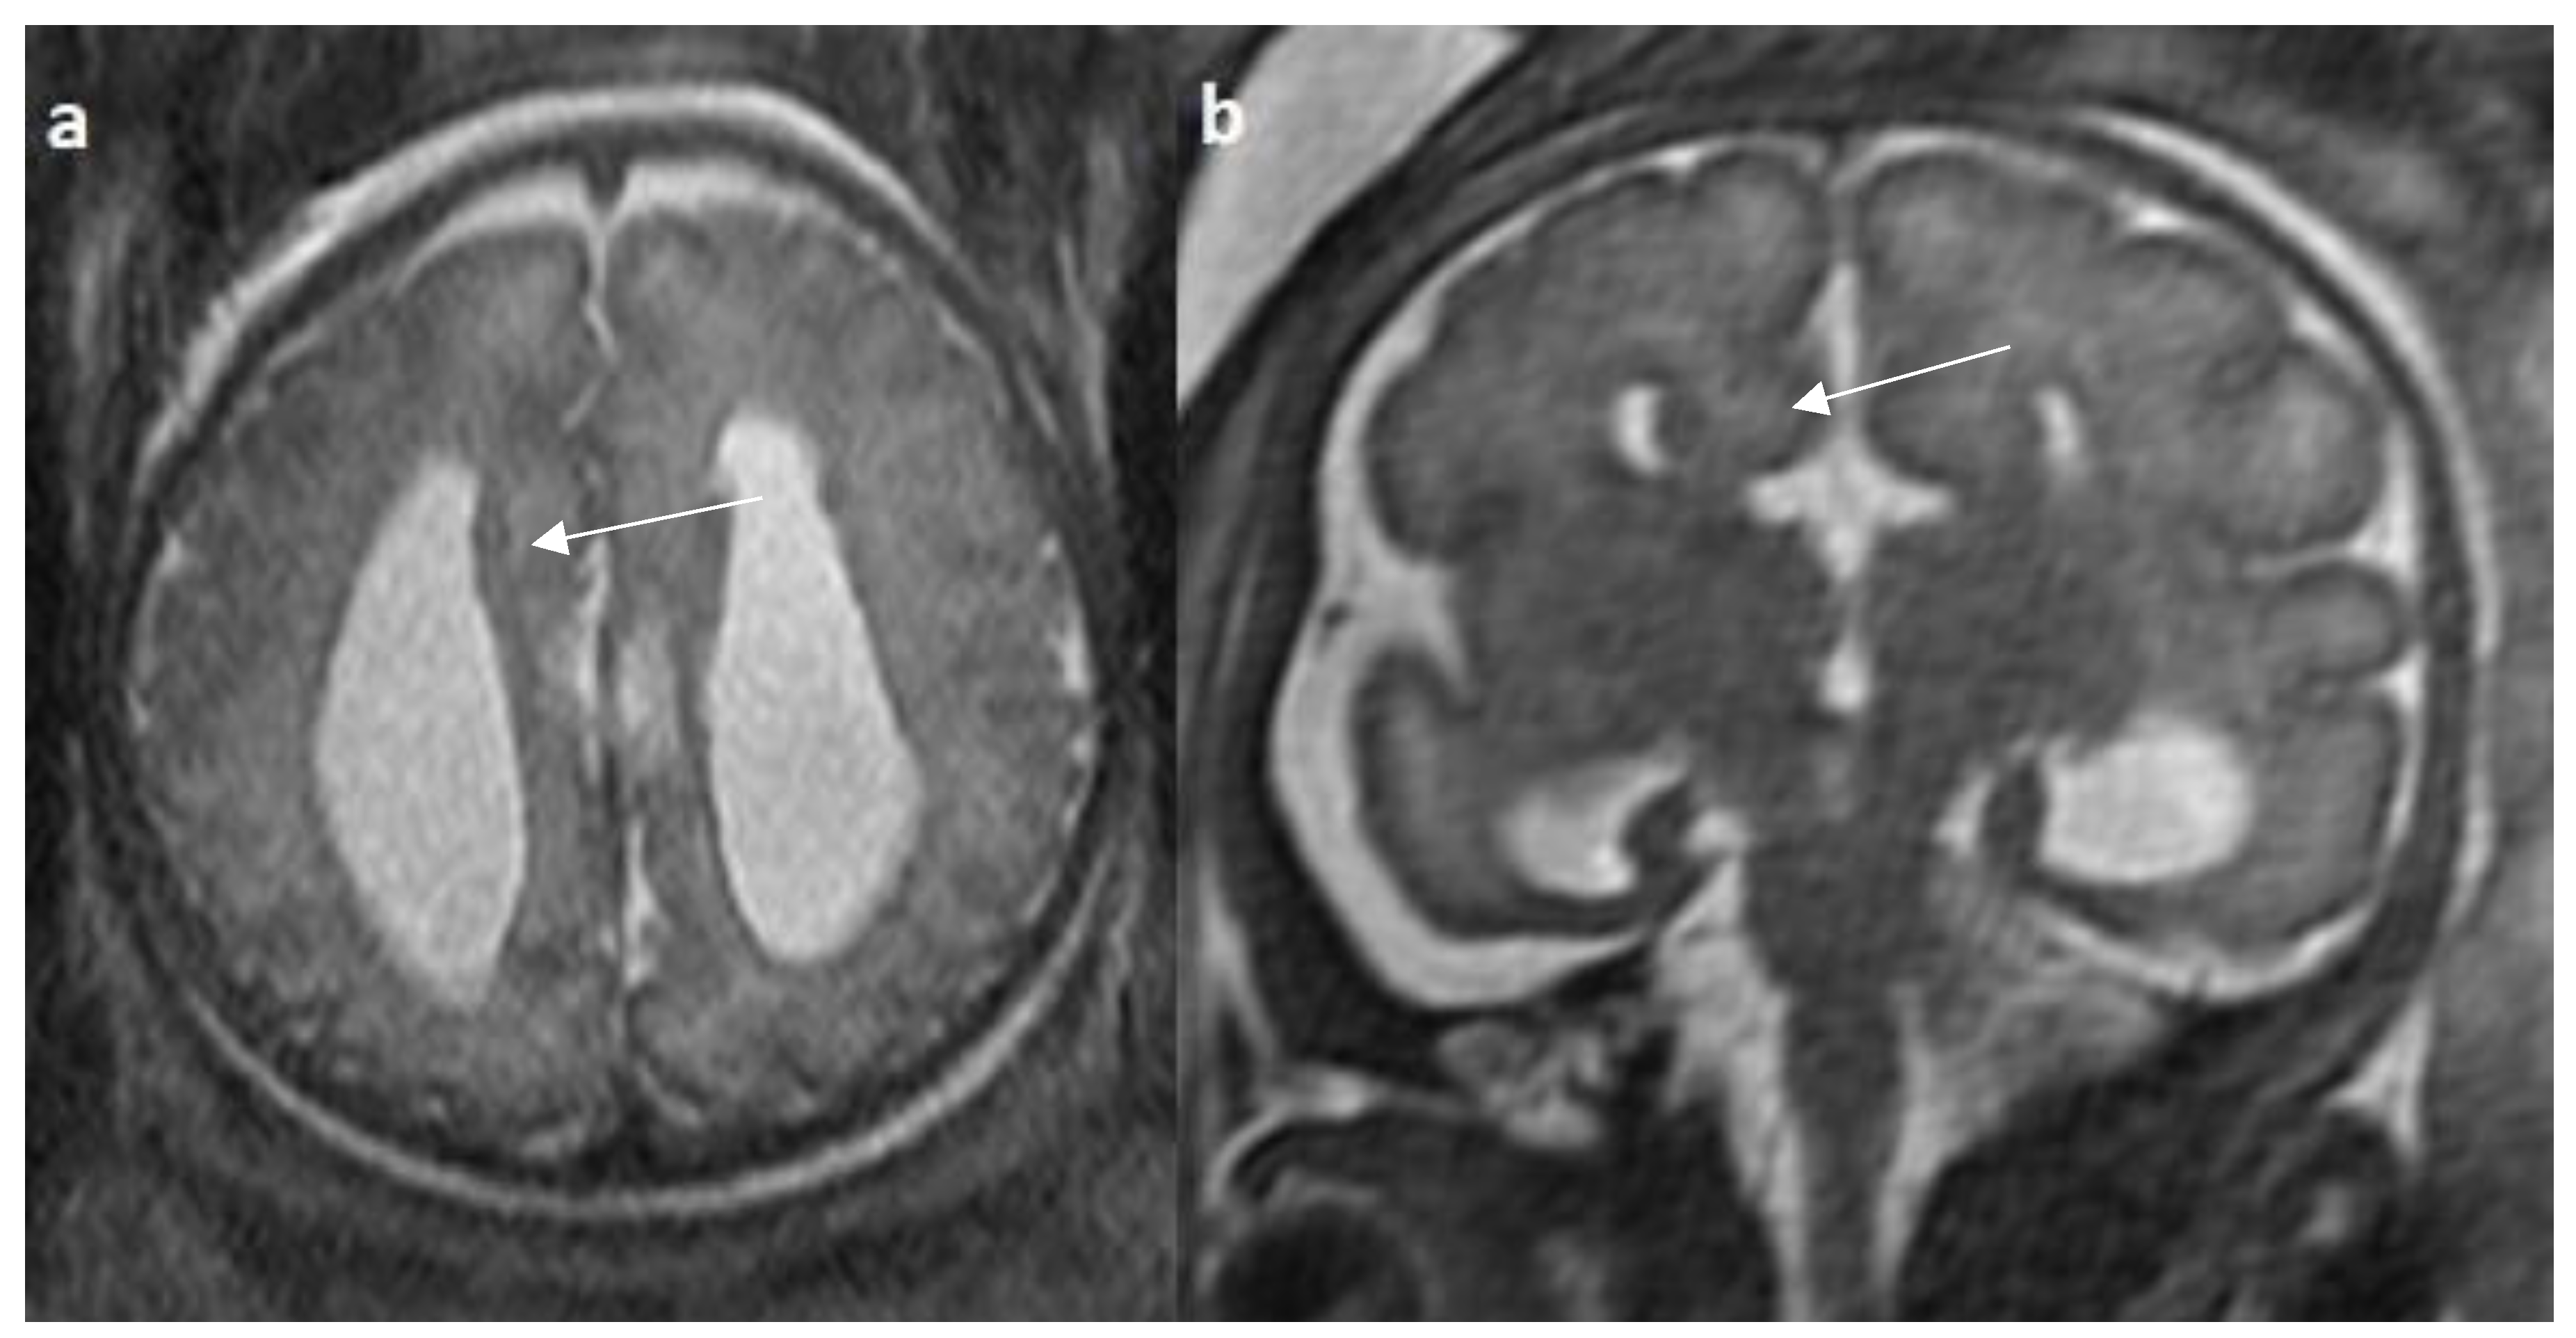

- Manor C, Rangasami R, Suresh I, Suresh S. Magnetic Resonance Imaging Findings in Fetal Corpus Callosal Developmental Abnormalities: A Pictorial Essay. J Pediatr Neurosci. 2020 Oct-Dec;15(4):352-357. [CrossRef]

- Hyun Yoo J, Hunter J. Imaging spectrum of pediatric corpus callosal pathology: a pictorial review. J Neuroimaging. 2013 Apr;23(2):281-95. [CrossRef]